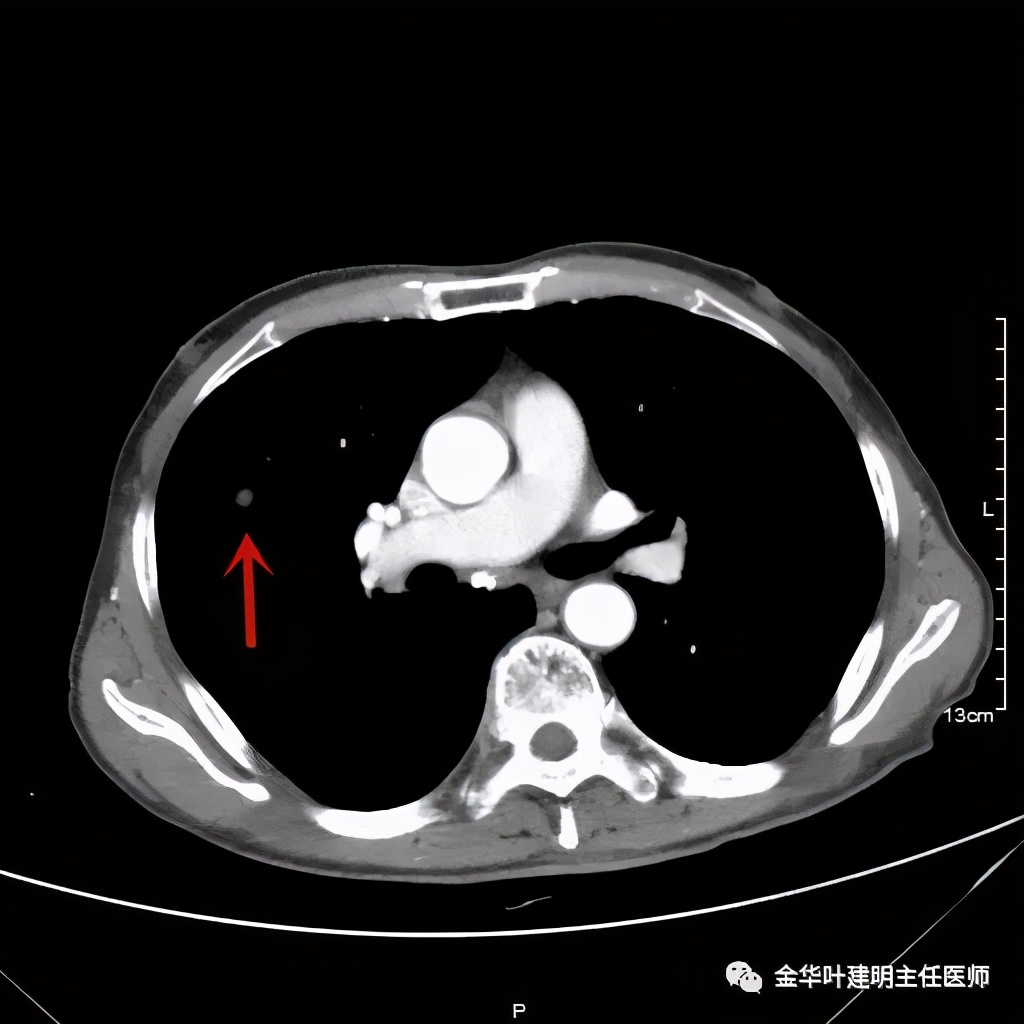

上图示病灶快要消失的层面

上图示病灶膨胀分叶,表面不平,像个土豆

上图示病灶密度不均,有偏低密度的区域

上图黄色箭头示空洞形成,病灶表面不平